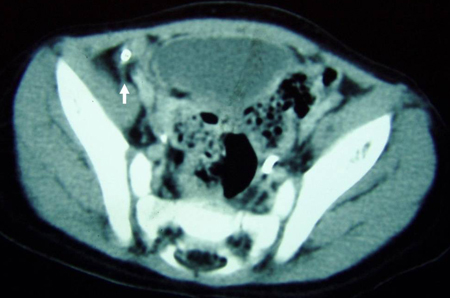

CT scan demonstrating intra-abdominal abscess consistent with perforated appendix

From the collection of Dr KuoJen Tsao; used with permission